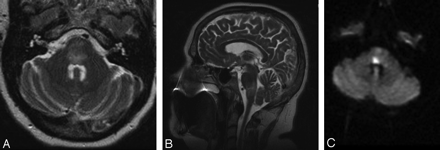

One hour after the procedure, the patient began to complain of “jumping” vision and unsteadiness associated with nausea and vomiting. On examination, she had a right internuclear ophthalmoplegia, mild right-sided facial weakness involving the lower motor neuron, drift of the left upper extremity, and diminished sensation in the left distal arm. An urgent MR imaging demonstrated T2-weighted abnormality in the pons and upper medulla and a diffusion-weighted imaging (DWI) abnormality within the dorsal pons (Fig 2) that was much smaller than the region of T2 change. The MR angiogram and MR venogram were notable for a dominant right transverse sinus and a patent basilar artery. These imaging findings were concerning for a brain stem infarction. She was admitted to the neurosurgical intensive care unit for aggressive fluid hydration and was given 10 mg of dexamethasone (Decadron) every 6 hours and 325 mg of aspirin daily.

A–C. Initial MR imaging after a change in the patient's neurologic examination. A, Axial T2-weighted MR imaging demonstrating diffuse edema within the pons. B, Sagittal T2-weighted MR imaging demonstrating the cranial-caudal extent of edema at the pontomedullary junction. C, Axial DWI MR imaging showing a region of restricted diffusion, highly suggestive of infarct, within the dorsal pons.

Overnight, she deteriorated further with complaints of severe diplopia bilaterally on lateral gaze. On examination, she had complete paralysis of horizontal gaze as well as increased right facial and left upper extremity weakness. She also reported some difficulty swallowing, and a formal swallowing evaluation confirmed moderate dysphagia. For the next 48 hours, she developed new weakness involving the left leg, and she had decreasing oxygen saturations and increasing stridor, requiring intubation and an eventual tracheostomy. Repeat MR imaging demonstrated diminished T2-weighted abnormality within the pons and evidence of hemorrhagic conversion on gradient-echo sequences. Another MR imaging examination performed 3 weeks later revealed diminished T2-weighted abnormality within the pons and medulla but continued DWI abnormality within the dorsal pons, extending in a linear wedge to the right ventral pontine surface. She was transferred to acute rehabilitation after 3 weeks on the neurosurgical service, at which time her hemiparesis and facial weakness were improving and the sensory deficits had resolved.

Follow-Up

Repeat MR imaging 3 months after IPSS demonstrated very scant T2-weighted abnormality, except in the region coinciding with the fixed DWI abnormality in the dorsal pons (Fig 3). At 6-month follow-up, she reported diminished diplopia but had persistent bilateral lateral gaze palsy. She did, however, have complete resolution of her right facial weakness and left-sided hemiparesis. In addition, her tracheostomy had been reversed and her swallowing was substantially improved.

MR imaging at 3 months after IPSS. Axial T2-weighted MR imaging demonstrating near-complete resolution of edema within the brain stem but a region of hyperintensity within the dorsal pons corresponding to the region of infarction.

In our 5½-year experience, 44 patients underwent IPSS after either an equivocal work-up or after previous failed surgery. The initial 35 consecutive patients sustained no complications as a result of the procedure, and the 8 most recent procedures have also been free of complications. However, 1 of 44 patients did sustain a partially reversible brain stem injury. After reviewing the literature, we believe that the prominent anterior pontomesencephalic veins seen in our patient during the right IPS venogram was an example of a variant pattern of venous drainage surrounding the brain stem and contributed to her injury. Whether this was from the catheter occluding venous outflow or from focal venous hypertension as a result of contrast injection remains unclear. There is some evidence of contrast reflux superiorly into the cranial aspect of the anterior mesencephalic vein instead of only inferior venous drainage (Fig 1B). This raises the possibility of some degree of outflow obstruction or slowing. During the procedure, the patient reported no symptoms, and there were no changes in the patient's examination or vital signs that would have caused us to terminate the test. The resulting injury on the first MR showed diffuse brain stem edema with a smaller region of actual infarction. The region of injury seen on T2-weighted sequences is consistent with our patient's neurologic examination with involvement of the fibers of pontomedullary cranial nerves (VI, VII, IX, and X), the paramedian pontine reticular formation, medial longitudinal fasciculus, portions of the corticospinal tract, medial lemniscus, and spinothalamic tracts. As the edema in the brain stem resolved, best seen on the evolution of T2-weighted sequences on serial MR imaging, the patient's sensory, motor, and lower cranial nerve deficits also resolved. The resulting infarct on the 3-month follow-up MR imaging confirmed a persistent abnormality on T2-weighted sequences within the dorsal pons that extends ventrally (Fig 3). The patient's neurologic examination after 6 months suggests that with the resolution of brain stem edema, only the fibers of the sixth cranial nerve, medial longitudinal fasciculus, and paramedian pontine reticular formation remain damaged. On the basis of the MR imaging findings, this is not surprising.